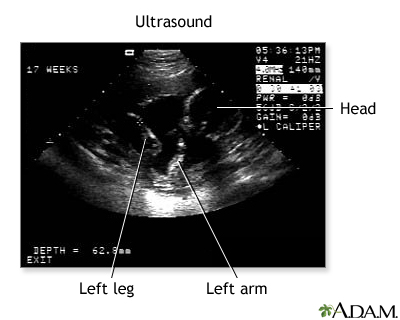

Procedure, part 3

Don't get your hopes up too much about this first, fleeting look at your baby. The black-and-white image you see on the computer screen is grainy, shadowy, and may look more like a test pattern than a baby-to-be. Your sonographer will walk you through what you're seeing by pointing out the fetus' developing heart, limbs, and head.